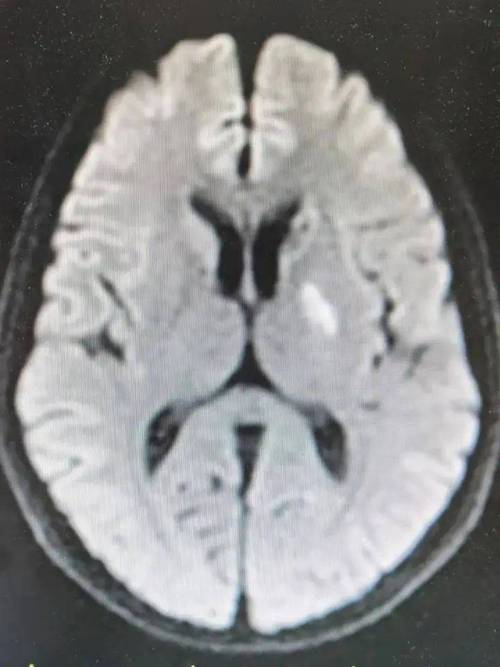

- DWI(弥散加权成像)序列:这是诊断超早期脑梗死的“金标准”,在发病几分钟到几小时内,DWI序列就能显示出明显的高信号(亮斑),几乎100%可以确诊急性脑梗死。

- FLAIR(液体衰减反转恢复)序列:在早期可能正常,但随着时间推移会显示高信号。